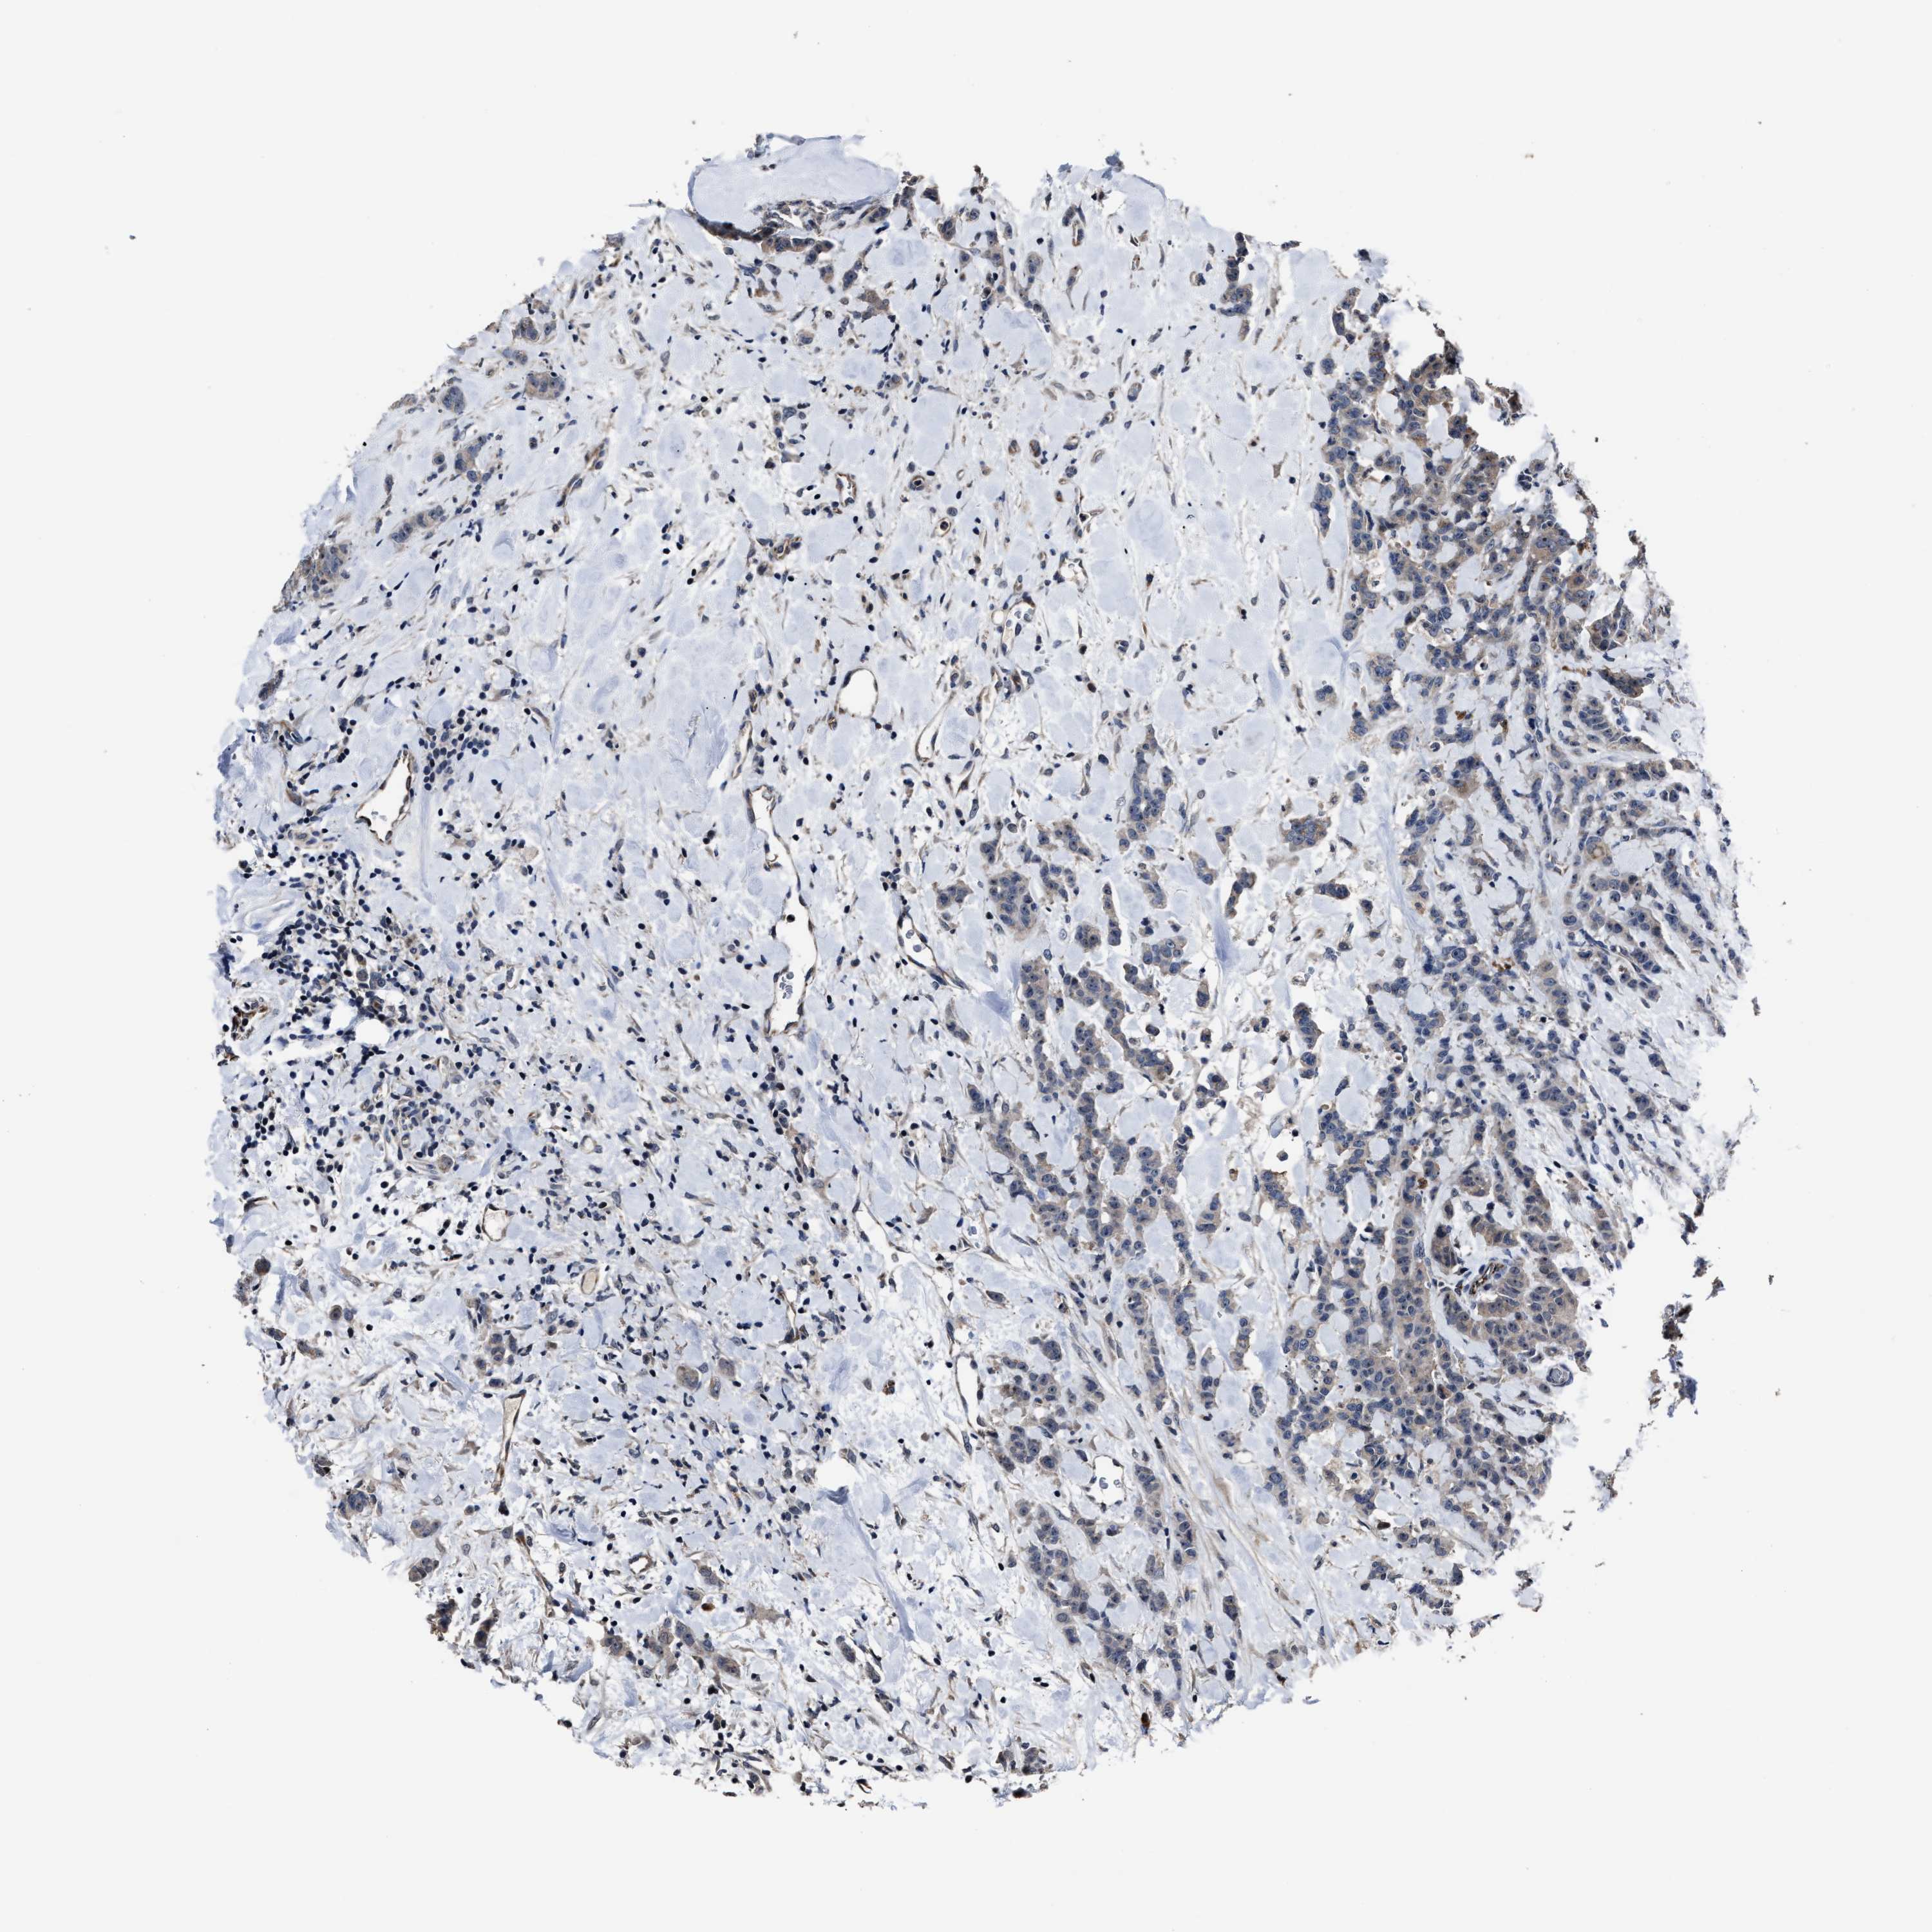

CANCER BREAST CANCER Show tissue menu

BRCA TCGA BRCA VALIDATION PROTEIN EXPRESSION